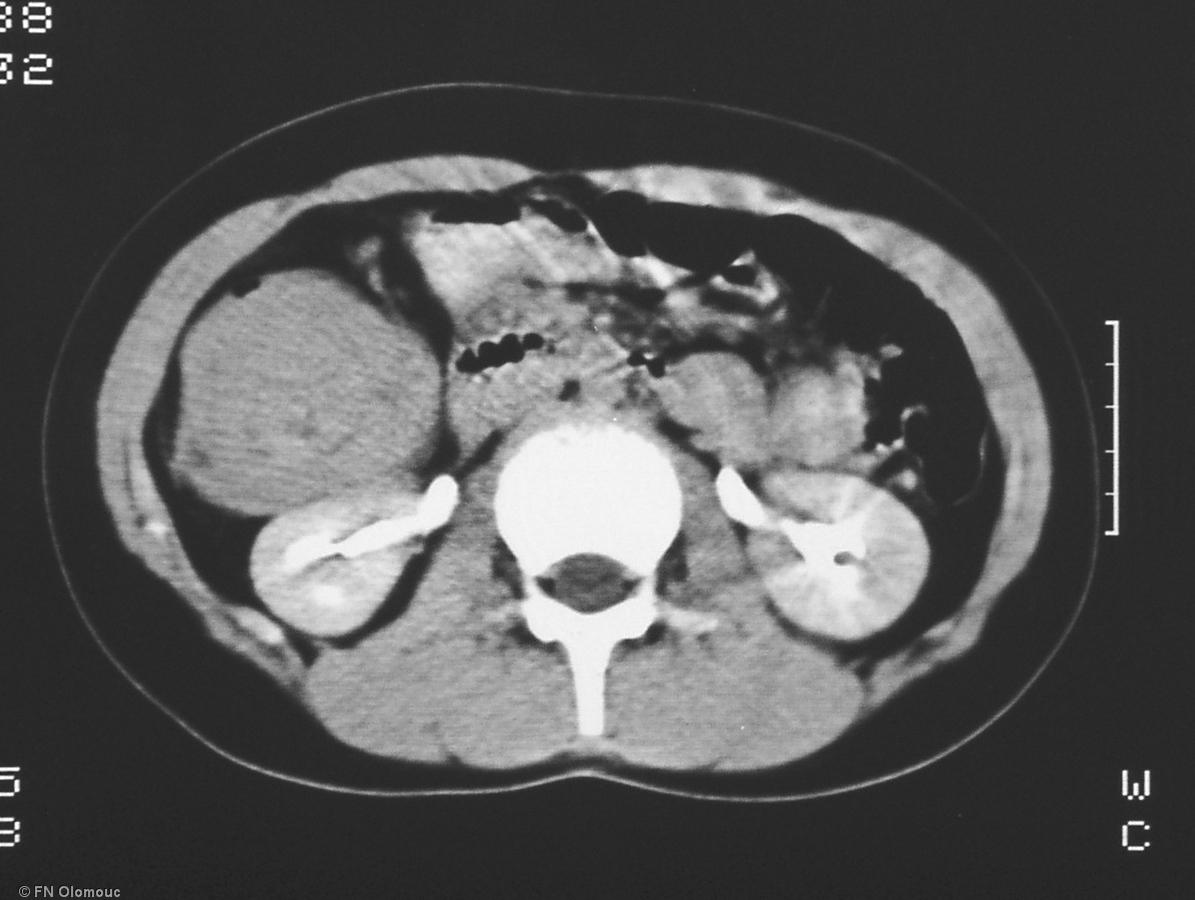

CT snímek břicha

CT snímek břicha.